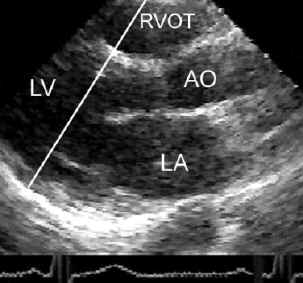

Correct positioning of M-mode cursor in the transthoracic parasternal long axis view to obtain the standard left ventricular M-mode tracing as shown above.